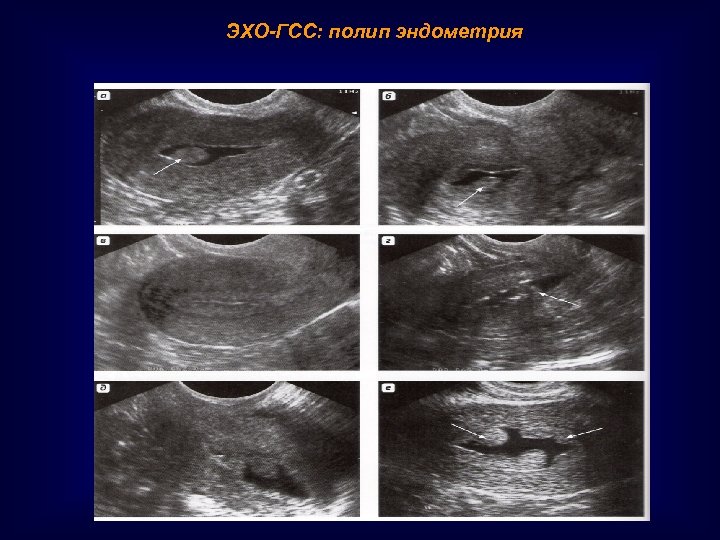

ЭХО-ГСС: полип эндометрия